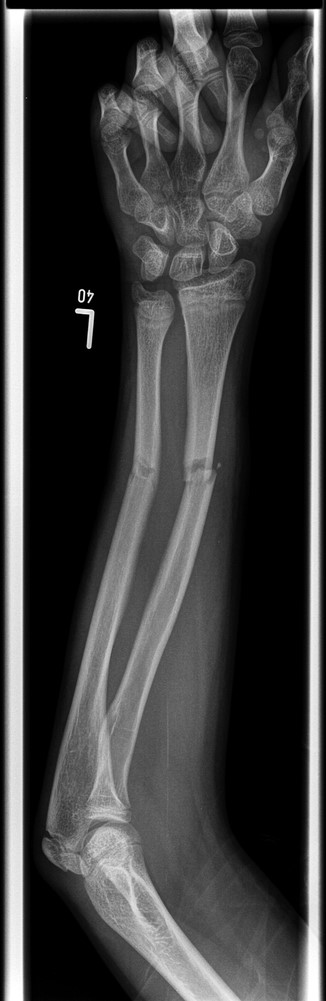

A 12-year-old male patient sustained a closed midshaft both-bone forearm fracture of their non-dominant arm from a fall on a trampoline (Figs 1 and 2). Anatomical reduction was achieved with a manipulation under anaesthesia (MUA), but it was noticed that there was a mechanical block to extension of the ring finger. The radius and ulna were therefore approached through separate incisions and it was discovered that the FDP was entrapped at the ulna fracture at the level of the musculotendinous junction. Following release the fingers regained a full range of motion and the patient went on to heal without further complication (Figs 3 and 4).

Three months post-operative lateral radiograph showing radiological union.